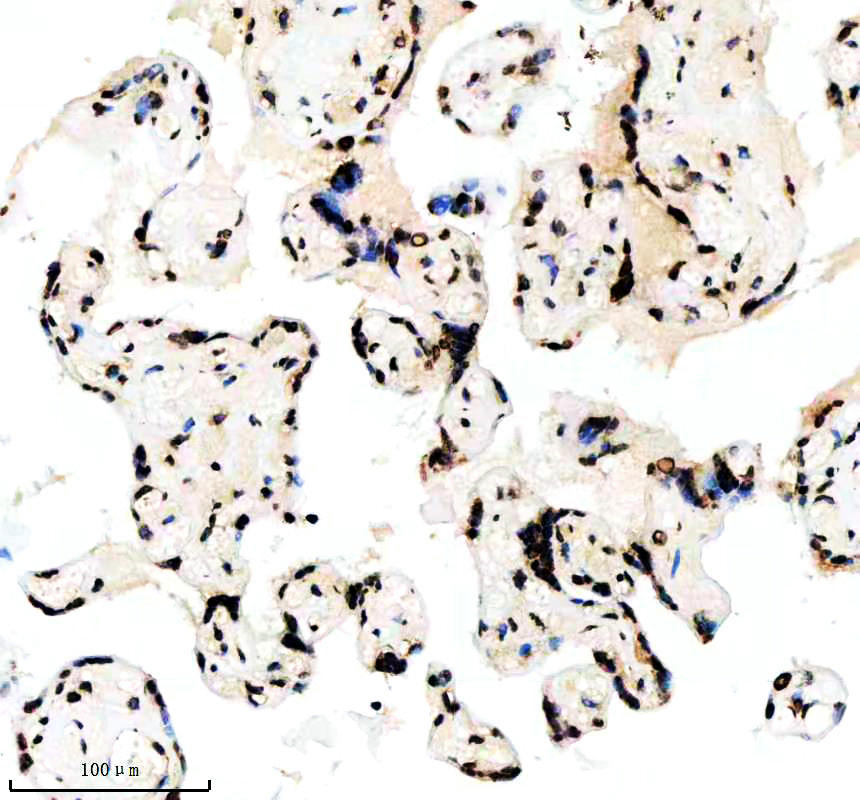

IHC analysis of Histone H3 (acetyl K14) using anti-Histone H3 (acetyl K14) antibody (BM4151) .

Histone H3 (acetyl K14) was detected in a paraffin-embedded section of human placenta tissue. The tissue section was incubated with rabbit anti-Histone H3 (acetyl K14) Antibody (BM4151) at a dilution of 1:200 and developed using HRP Conjugated Rabbit IgG Super Vision Assay Kit (Catalog # SV0002) with DAB (Catalog # AR1027) as the chromogen.

IHC analysis of Histone H3 (acetyl K14) using anti-Histone H3 (acetyl K14) antibody (BM4151) .

Histone H3 (acetyl K14) was detected in a paraffin-embedded section of human placenta tissue. The tissue section was incubated with rabbit anti-Histone H3 (acetyl K14) Antibody (BM4151) at a dilution of 1:200 and developed using HRP Conjugated Rabbit IgG Super Vision Assay Kit (Catalog # SV0002) with DAB (Catalog # AR1027) as the chromogen.